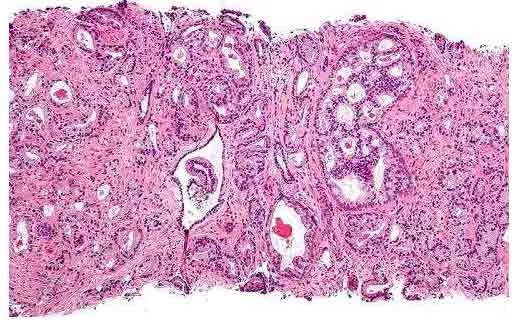

Patient Prostate Tissue Used to Create Unique Model of Prostate Cancer Biology December 15, 2016 For the first time, researchers have been able to grow, in a lab, both normal and primary cancerous prostate cells from a patient, and then implant a million of the cancer cells into a mouse to track how the tumor progresses. The achievement, say researchers at Georgetown University Medical Center who led the research, represents a critical advance in the effort to understand the origin and drivers of this puzzling cancer. Read more.Source: Medical Xpress Prostate Cancer News

For the first time, researchers have been able to grow, in a lab, both normal and primary cancerous prostate cells from a patient, and then implant a million of the cancer cells into a mouse to track how the tumor progresses. The achievement, say researchers at Georgetown University Medical Center who led the research, represents a critical advance in the effort to understand the origin and drivers of this puzzling cancer. Read more.Source: Medical Xpress